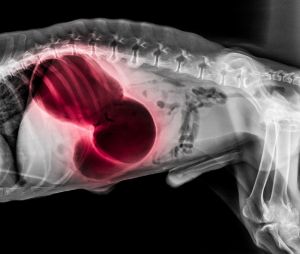

Torze, neboli přetočení žaludku, je jednou z nejčastějších příčin úmrtí psů. Přibližně polovina psů uhyne dříve, než vůbec dojde k léčbě a skoro jedna čtvrtina umírá v prvních sedmi dnech po stanovení diagnózy. Nejvíce riziková skupina jsou velká plemena, ale nevyhýbá se ani malým pejskům.